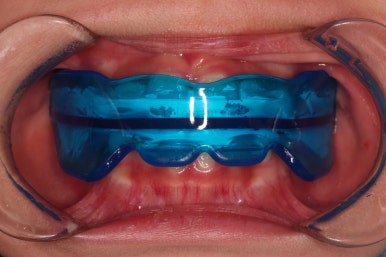

3, 치료경과

장치의 모습이 운동선수들이 사용하는 마우스피스와 같이 생기긴 했으나 내부 구조나 치열을 잡아주는 부분의 기능이 다릅니다.

프리올소는 앵글씨 3급 부정교합에도 사용하지만, 오픈 바이트나 앵글씨 2급 부정교합에도 사용합니다.